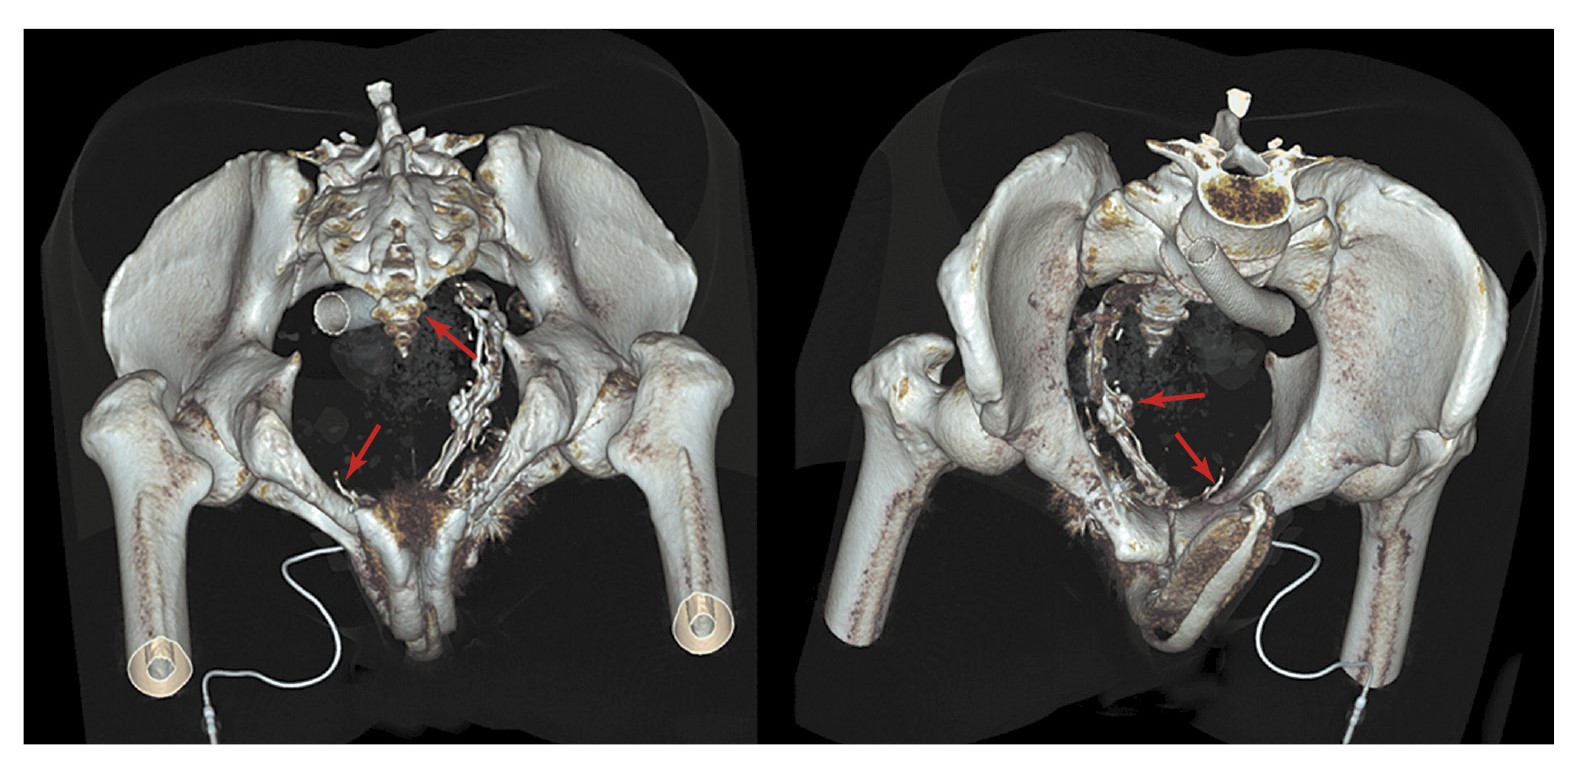

С целью подтверждения венозной утечки и оценки венозной анатомии половой системы пациенту проведена МСКТ-кавернозография. Фармакологическую стимуляцию осуществляли посредством введения 10 мкг простагландина интракавернозно. Получены изображения в нативную фазу (до введения контрастного вещества), а также через 30 с, 1, 3 и 5 мин после интракавернозного введения контрастного препарата (йогексола 350 мг/мл, 50 мл). По данным КТ в области наружной и внутренней поверхностей правой лобковой кости определяются множественные гиперденсивные структуры, вероятно, эмболизационные спирали (рис. 2).

Рис. 2. Данные МСТК-кавернозографии больного К. Стрелкой указаны гиперденсивные инородные структуры (вероятно, спирали) в области правой лобковой кости.

В левой общей подвздошной вене с выходом в нижнюю полую вену определяется стент (рис. 3).

Рис. 3. Данные МСТК-кавернозографии больного К. Стрелкой указан стент в левой общей подвздошной вене.

Размеры, форма и ход кавернозных тел обычные. Отток контрастного препарата нарушен. На 30-й секунде определяется наличие минимального сброса контрастного препарата в перипростатическое сплетение через вену левой ножки ПЧ. На 1-й минуте отмечаются умеренное контрастирование вен в области левой ножки ПЧ и существенный сброс контрастного препарата через вены правой ножки ПЧ и вены тазового сплетения справа (рис. 4).

Рис. 4. Данные МСКТ-кавернозографии больного К. Стрелкой указана утечка контрастированной крови из кавернозных тел в области ножки ПЧ через вены правого кавернозного тела в тазовое сплетение.

На 3-й минуте сохраняется небольшой сброс контрастного препарата через вены левой ножки ПЧ, отмечается усиление сброса контрастного препарата через вены правой ножки ПЧ и вены тазового сплетения справа (рис. 5). На 3-й минуте отмечается появление небольшого сброса контрастного препарата в общую бедренную вену справа через 2 небольших коллатерали диаметром 1,5 и 3 мм.

Рис. 5. Утечка контрастированной крови из кавернозных тел справа и появление небольшого сброса слева.

На 5-й минуте сохраняются описанные патологические венозные дренажи без существенной динамики. 3D-реконструкция КТ-картины нарушения вено-окклюзионного механизма ПЧ приведена на рис. 6. Отмечены резкий венозный сброс справа и умеренный венозный сброс слева.

Рис. 6. 3D-реконструкция КТ-кавернозографии. Стрелками указаны значительный сброс контрастированной крови из кавернозных тел через венозный коллектор простатического сплетения в правую общую подвздошную вену (3–5-я минута после введения контрастного препарата).